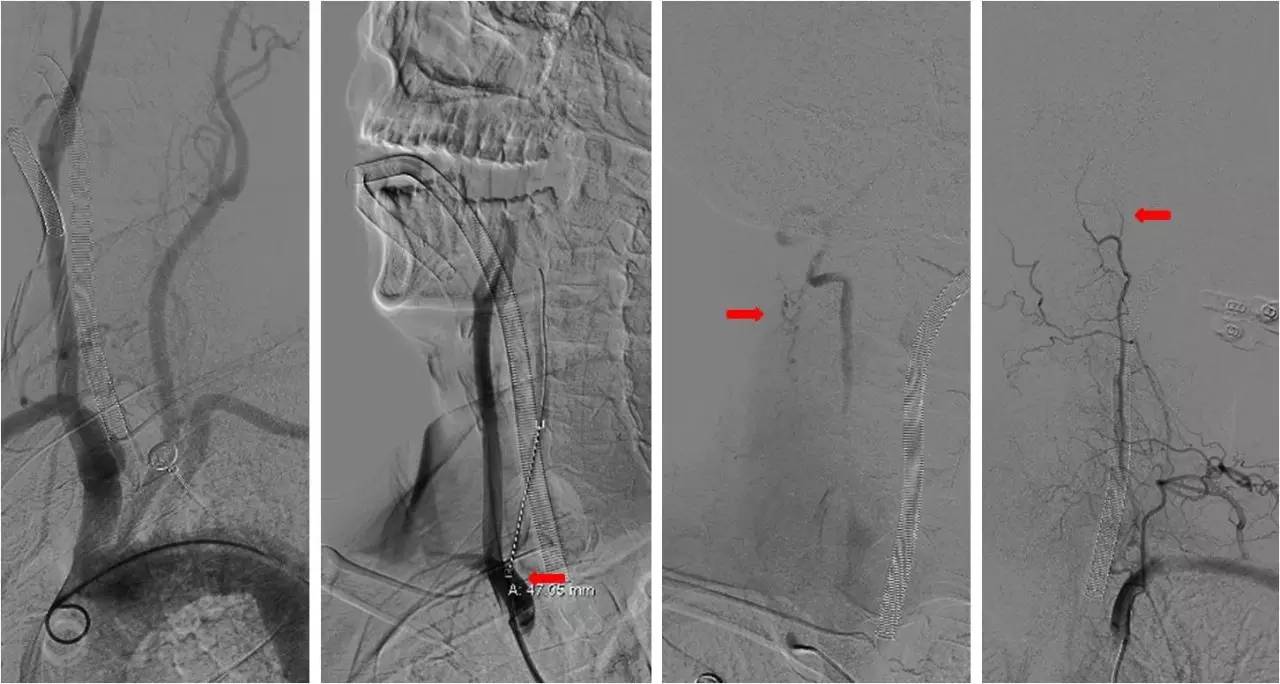

》术中造影

★右侧椎动脉起始端长段闭塞,右侧颈深动脉向右侧椎动脉供血,远端基底动脉不显影;左侧椎动脉纤细,V3段以远不显影。

★右侧颈总动脉正侧位,可见右侧枕动脉通过肌支向右侧椎动脉供血,远端基底动脉不显影。

》治疗过程

★2.0x20 mm球囊扩张后,右椎动脉起始段见前向血流,将6F navien颅内支撑导管送至V3段造影,见V4段有血栓,基底动脉闭塞 ;

★Solitaire 6.0x20 mm取栓支架到位造影,取栓两次后基底动脉再通。

★取栓后处理椎动脉起始端的狭窄,椎动脉开口处先放置一枚球扩支架,造影见支架远端仍有狭窄,将Solitaire 6.0x20 mm贴敷在狭窄段,造影见前向血流改善(TICI分级 3级)。